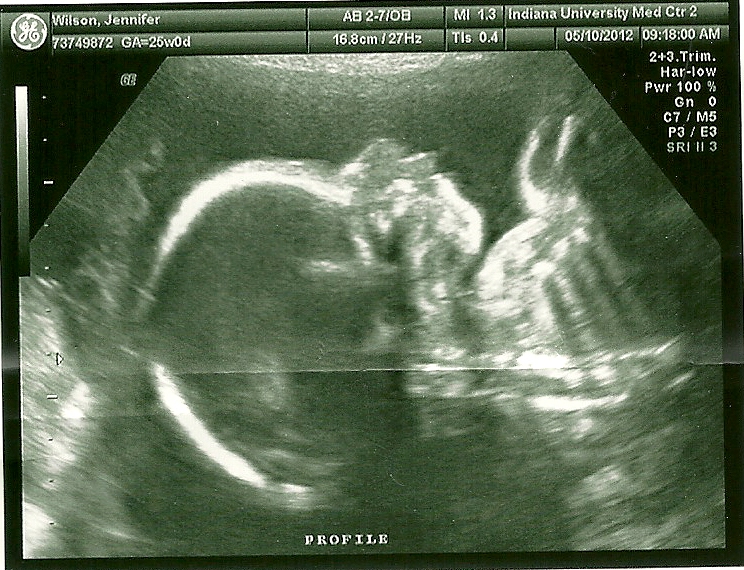

We started the ultrasound anyway, and right

away- surprise, surprise, baby number two is STILL a boy (he’s never been very

modest).

We were then able to get some of the

fun ultrasound pictures done, like the baby’s profile shots. Those are the

cutest don’t you think? When you can see their little noses and lips. Darling. We

tried to get a shot of his face using the 3D ultrasound, but it didn’t really

work out. This is the second time we’ve tried and both times he hides his face…

I guess he wants his big reveal to be a surprise. Haha.